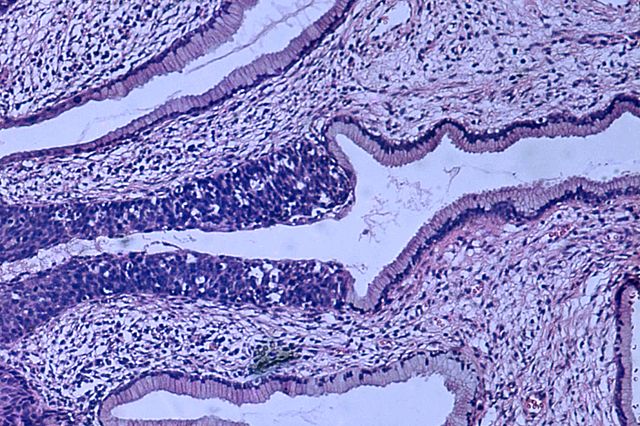

Бројот на заболени од рак на грлото на матката расте, ХПВ вакцина и скрининг се клучни за превенција

Најмладите пациентки на кои им бил дијагностициран рак на грлото на матката во Македонија имаат само 18 години, а средната возраст за поставување на дијагнозата е 55 години. Загрижувачкиот податок беше соопштен на настанот по повод Неделата за подигнување на свеста за борбата против овој вид карцином, организиран од Македонското лекарско друштво и Македонското здружение за цервикална патологија.

Бројот на жени кои заболуваат од рак на грлото на матката расте од година во година. На Клиниката за онкологија, во 2024 година биле третирани 74 пациентки, а лани бројката изнесувала 122.

Директорката на Клиниката за гинекологија, професор д-р Ирена Алексиоска-Папестиев, цитираше студија од Институтот за епидемиологија која покажува дека во периодот од 2016 до 2023 година биле дијагностицирани 2.263 пациентки. Таа посочи дека 540 од нив, што е речиси 24 отсто, починале.

„Загрижува што овој карцином се појавува кај се помлади пациентки и е целосно превентабилен. Целта е да ја зголемиме свеста кај јавноста“, додаде таа.

Експертите потенцираа дека ризикот од рак на грлото на матката значително се намалува со примање на ХПВ вакцината и со редовен скрининг, кој би требало наскоро да се воведе и во Македонија.